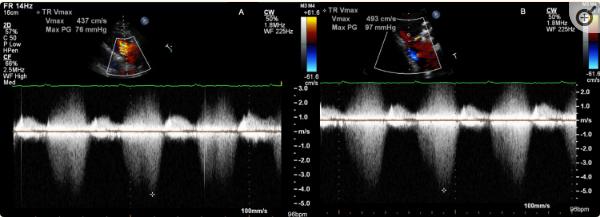

在整个住院期间,患者的白细胞计数在9000-16000之间,有7次MRSE血培养呈阳性。初始心电图显示窦性心动过速,一级房室传导阻滞,QRS持续时间为88 ms。经胸超声心动图(TTE)显示射血分数为55-60%,无赘生物迹象。有中度三尖瓣反流(TR)和严重肺动脉高压,肺动脉(PA)收缩压70 mm Hg,没有右心室(RV)或RA扩大的证据。此外,TR多普勒显示在收缩期中期出现“双匕首”外观(图1)。

图1、RV流入视图的TTE图像。A组三尖瓣多普勒波形,Vmax为4.37 m/s,最初描述为“三尖瓣反流”。在白色星形图中,有双囊膜穿过三尖瓣,继发于VSD。B组双匕首包膜,Vmax 4.93 m/s,发生于收缩期中期,提示室间隔缺损